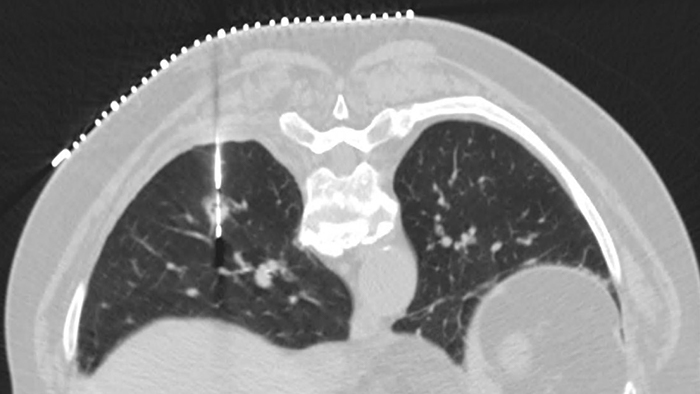

Deslice la barra para comparar imágenes sin y con Precise Image.

Experimente una calidad de imagen que se puede lograr hasta con 80% menos de dosis, hasta 85% menos ruido y hasta 60% de detectabilidad mejorada de bajo contraste.3 Precise Image tiene una apariencia de imagen familiar que se asemeja mucho a la retroproyección filtrada (filtered back projection, FBP). También verá la mejor resolución de bajo contraste de su clase.